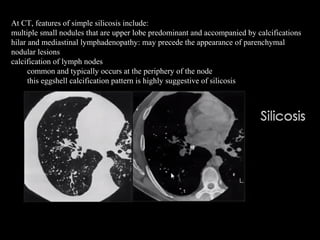

At CT, features of simple silicosis include:

multiple small nodules that are upper lobe predominant and accompanied by calcifications

hilar and mediastinal lymphadenopathy: may precede the appearance of parenchymal

nodular lesions

calcification of lymph nodes

common and typically occurs at the periphery of the node

this eggshell calcification pattern is highly suggestive of silicosis

Silicosis is a fibrotic pneumoconiosis that is caused by the

inhalation of fine particles of crystalline silicon dioxide

(silica). Occupations such as mining, quarrying, and tunneling are

associated with silicosis.

The classic form is much more common than the acute form and

can be classified as simple or complicated, according to the

radiographic findings:

simple silicosis: pattern of small and round or irregular opacities

complicated silicosis: large conglomerate opacities that equate

to progressive massive fibrosis

Silicosis in a 56-year-old man who worked for 25 years as a

stonecutter. (a) Chest radiograph shows multiple variable-sized nodular

lesions in both lungs, predominantly in the upper and middle

zones. (b) Axial thin-section CT scan (1.0-mm-thick section) obtained at

the level of the azygos arch shows multiple small nodules with a

perilymphatic (centrilobular plus subpleural) distribution in the upper

lobe of both lungs. Note the tendency toward coalescence of the nodules

in the lung periphery (arrows).

Radiography of silicosis and CWP are similar:

Simple: micronodules < 1 cm, upper lungs, hilar/mediastinal lymphadenopathy, egg shell

calcifications

Complicated known as progessive massive fibrosis (PMF): aggregation of nodules into

large masses, may cavitate

Increased risk for TB